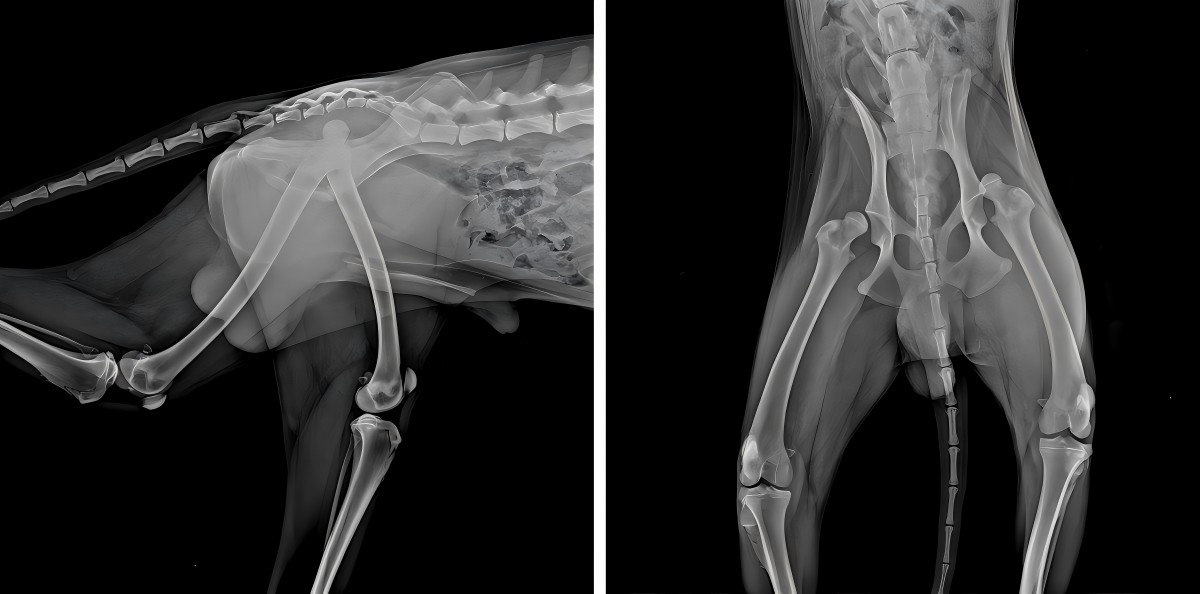

Diagnosis pencitraan DR

Dislokasi femoralis bilateral